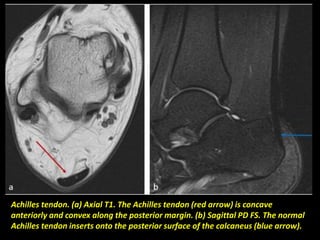

Achilles tendon. (a) Axial T1. The Achilles tendon (red arrow) is concave

anteriorly and convex along the posterior margin. (b) Sagittal PD FS. The normal

Achilles tendon inserts onto the posterior surface of the calcaneus (blue arrow).

Achilles tendon. (a)Axial T1. The Achilles tendon (red arrow) is concave anteriorly and convex along the posterior margin. (b) Sagittal PD FS. The normal Achilles tendon inserts onto the posterior surface of the calcaneus (blue arrow).